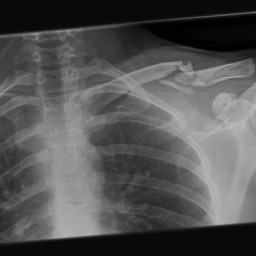

What do clavicle fractures look like on X-ray?

Below are examples of typical fractures that benefit from surgery.